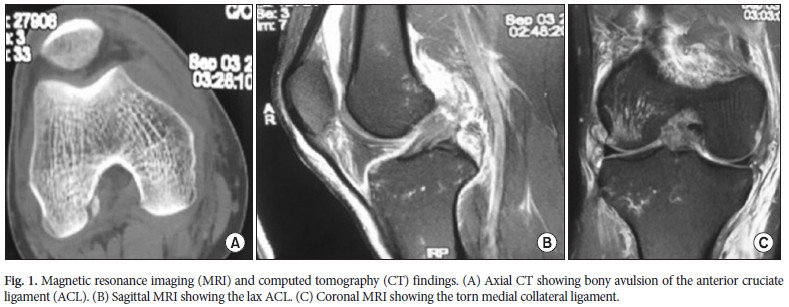

L'avulsion osseuse n'était pas apparente sur une radiographie standard antéropostérieur et latérale. Sur l'imagerie par résonance magnétique (IRM) et tomodensitométrie (CT), le fragment pouvait être vu distinctement sur la coupe axiale (Fig. 1A). Le LCA était en continuité sur l’IRM mais apparaissait relâché (Fig. 1B). Le LCM présentait une lésion au niveau intermédiaire de la structure (Fig. 1C). Il n'y avait aucune preuve d'une atteinte du ménisque latéral à l’IRM.

L'avulsion osseuse n'était pas apparente sur une radiographie standard antéropostérieur et latérale. Sur l'imagerie par résonance magnétique (IRM) et tomodensitométrie (CT), le fragment pouvait être vu distinctement sur la coupe axiale (Fig. 1A). Le LCA était en continuité sur l’IRM mais apparaissait relâché (Fig. 1B). Le LCM présentait une lésion au niveau intermédiaire de la structure (Fig. 1C). Il n'y avait aucune preuve d'une atteinte du ménisque latéral à l’IRM.

Dans la plupart des cas signalés, le traumatisme à grande vélocité s’est produit lorsque le genou était soumis à des contraintes en flexion, rotation interne et varus. Dans leur cas clinique, le patient a signalé que son genou était dans une position fléchie et en rotation externe immédiatement après la blessure. Ils ont observé des ecchymoses d’aspect médial et antérieur du genou lors de la première visite. Le possible mécanisme lésionnel, compte tenu des blessures du patient, fut une flexion et rotation externe. Les lésions se sont sans doute succéder du compartiment médial vers le latéral : LCM => LCA => ML. Le fragment d’os n’apparaissait pas sur les radiographies standards antéropostérieur et latéral. Les coupes axiales en TDM montraient l'avulsion osseuse et la continuité du fragment avec le LCA. L’IRM a démontré un LCA intact avec un œdème de la moelle osseuse au niveau du condyle fémorale latérale. Malgré sa rareté, ces données indiquent qu’une avulsion osseuse fémorale du LCA peut survenir chez l'adulte.

Dans la plupart des cas signalés, le traumatisme à grande vélocité s’est produit lorsque le genou était soumis à des contraintes en flexion, rotation interne et varus. Dans leur cas clinique, le patient a signalé que son genou était dans une position fléchie et en rotation externe immédiatement après la blessure. Ils ont observé des ecchymoses d’aspect médial et antérieur du genou lors de la première visite. Le possible mécanisme lésionnel, compte tenu des blessures du patient, fut une flexion et rotation externe. Les lésions se sont sans doute succéder du compartiment médial vers le latéral : LCM => LCA => ML. Le fragment d’os n’apparaissait pas sur les radiographies standards antéropostérieur et latéral. Les coupes axiales en TDM montraient l'avulsion osseuse et la continuité du fragment avec le LCA. L’IRM a démontré un LCA intact avec un œdème de la moelle osseuse au niveau du condyle fémorale latérale. Malgré sa rareté, ces données indiquent qu’une avulsion osseuse fémorale du LCA peut survenir chez l'adulte.